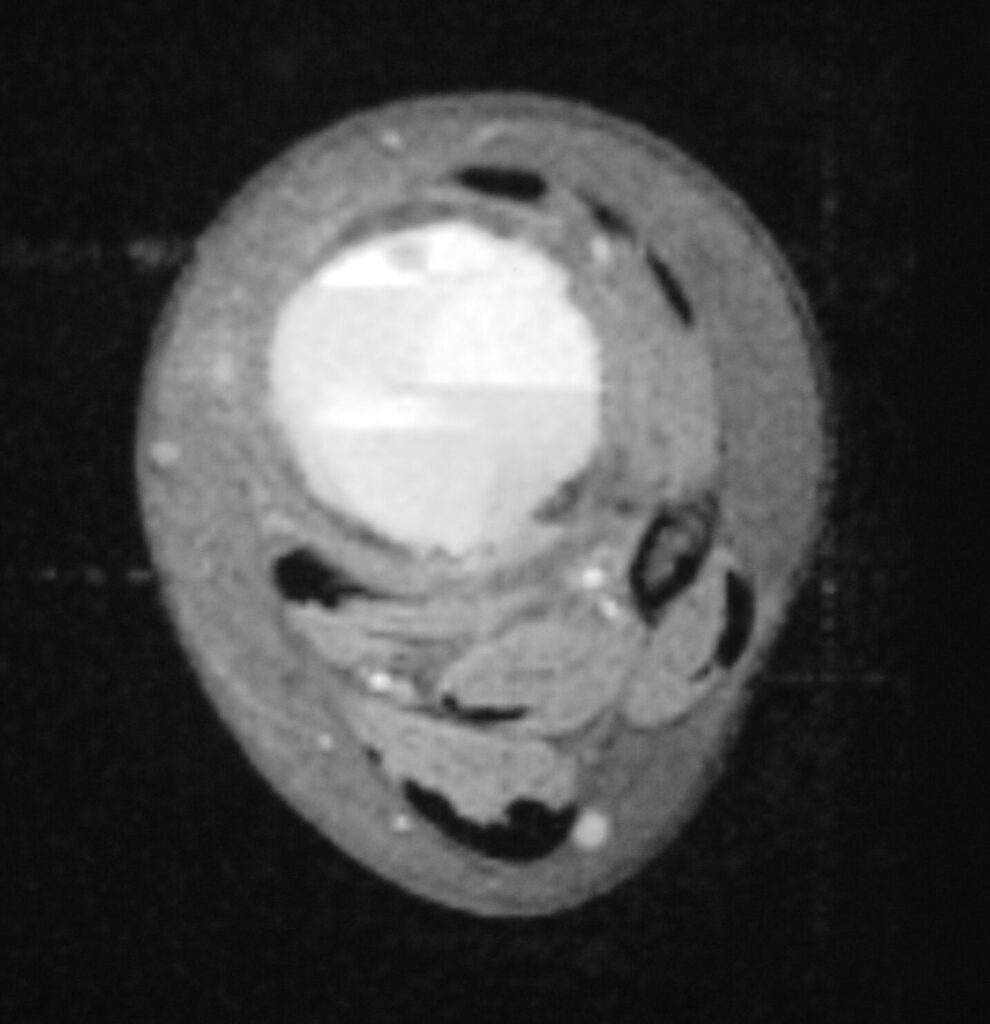

MRI

- Geographic well circumscribed

- High signal on T2 weighted MRI images

- Fluid/Fluid level (T2) are highly characteristic

Fig 2 a-e. MRI of an ABC of Distal Tibia: Fig 2 a-c: geographic cystic expansile lesion with fluid-fluid levels. The fluid-fluid levels are caused by bleeding into the cavities. The blood collects and the degredation products settle to the gravity dependent areas of the cavities. This shows up as fluid-fluid levels on the MRI. Fig 2 d,e: This is a gadolinium enhanced MRI of the ABC of the distal tibia. There is peripheral and septal enhancement indication cyst formation. The contrast outlines the cystic cavities but does not enter into the center

Fig 2c: Axial T2 weighted MRI of an ABC